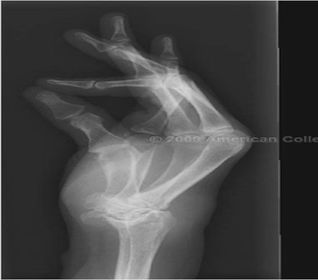

| PA Wrist | wrist externally rotated - joint spaces closed, proximal metacarpals superimposed, carpals superimposed radiocarpal joint is closed |